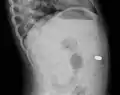

AP X ray showing a 9mm battery in the intestines

Lateral X ray showing a 9mm battery in the intestines